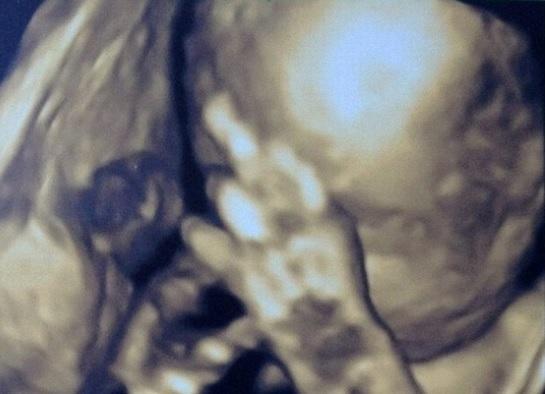

"Nu mă mai fotografia!" Gestul obscen pe care un făt l-a făcut în pântecele mamei, în timpul ecografiei - FOTO